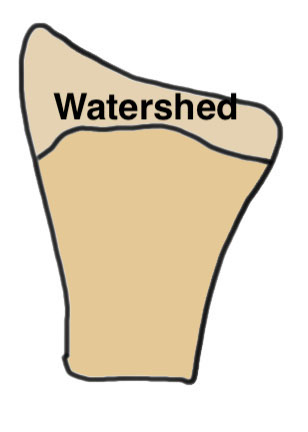

- ensure not beyond watershed line to avoid flexor tendon irritation / rupture

Volar rim fractures

Definition

Very distal fractures

Need distal plates

Low profile plates to protect flexor tendons

Technique

Plate sits distal to watershed line

- variable angle screws

- sit in subchondral bone

- can cause flexor tendon irritation and may need removal

Outcomes

Lari et al Eur J Orthop Surg Traumatol 2023

- systematic review of surgical treatment of volar rim fractures

- 26 studies and 600 patients

- implant removal 22%

- flexor tendon irritation 6%